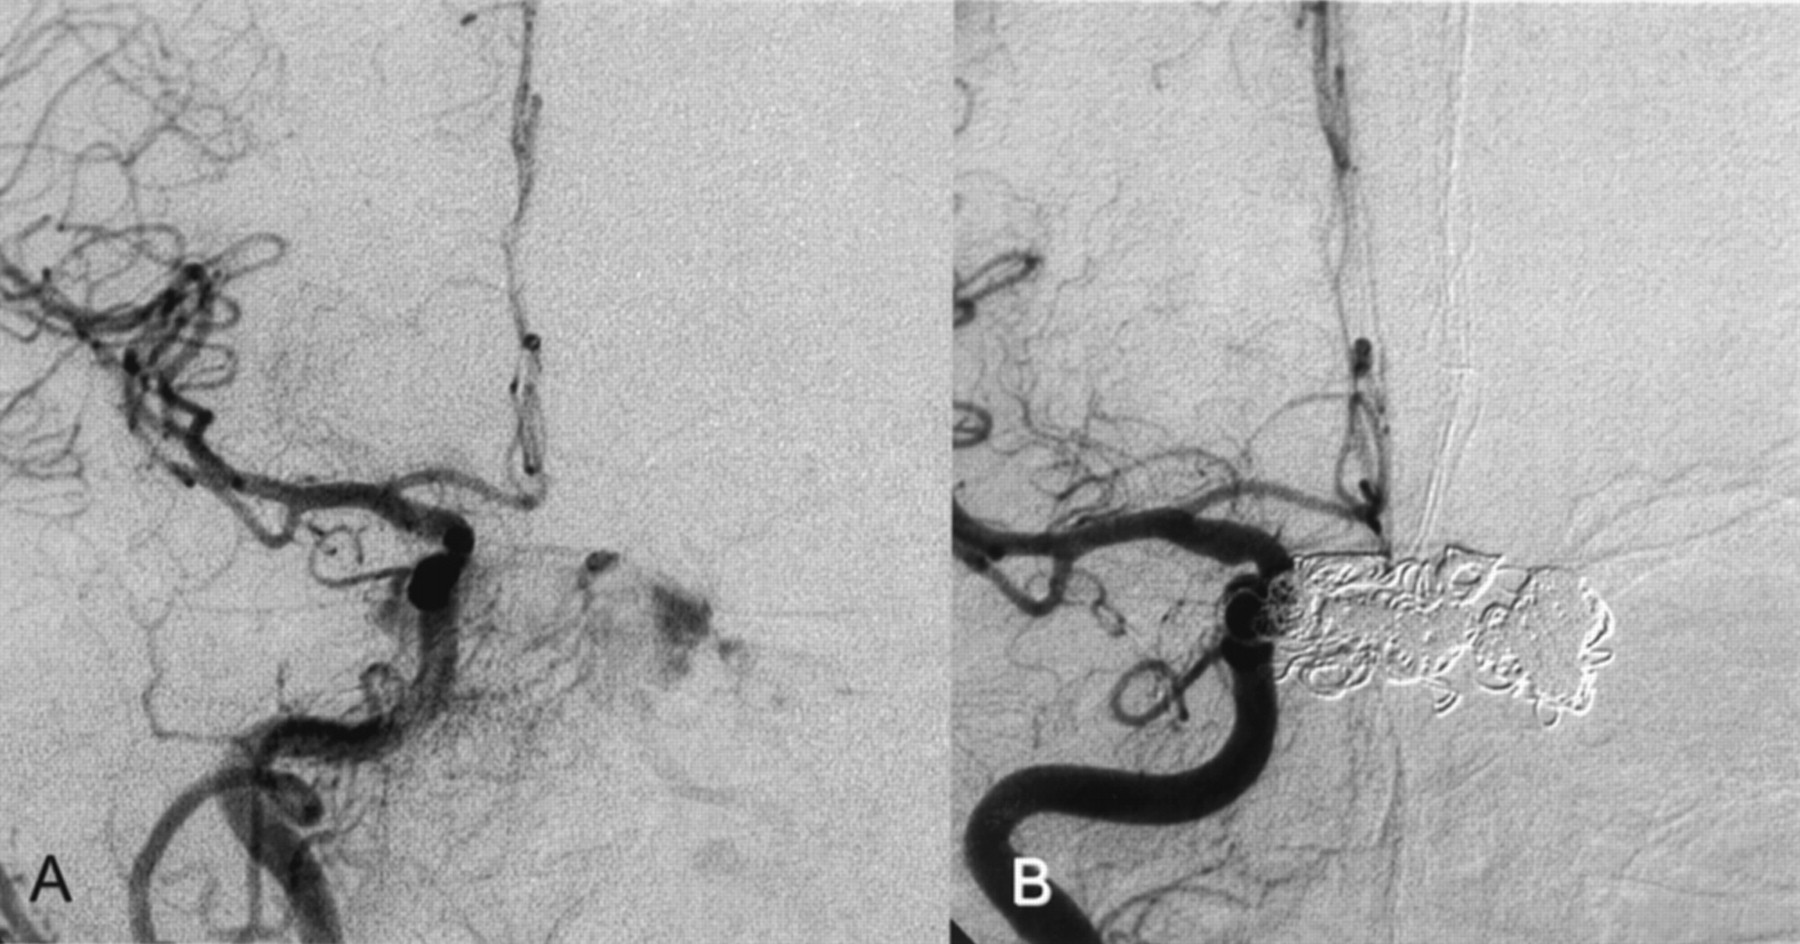

Two months before admission, a 74-year-old woman developed diplopia, exophthalmus on the left side, scotomas, left visual blur, and left conjunctival injection. MR imaging, MR angiography, CT, and duplex sonography revealed a CCF. At the time of admission, the patient had exophthalmus on the left, visual disturbance, diplopia, bilateral abducens nerve palsy, and left oculomotor nerve palsy. Angiography revealed a Barrow type D CCF with bilateral fistulae of the cavernous sinus fed by multiple meningeal branches of the external carotid artery on both sides, by the anterior meningeal branch of the left vertebral artery, and by the internal carotid artery on the left side (Figs 1 and 2). The CCF drained from the cavernous sinus into the right SOV, the left pterygoid venous plexus, the left inferior petrosal sinus, and via cortical veins into the straight sinus and the lateral sinuses on both sides. The right inferior petrosal sinus could not be detected. In contrast to the initial MR angiography performed 4 weeks earlier, the angiography showed the left SOV being thrombosed.

Left CCA.

A, Before treatment.

B, After successful CCF treatment.

However, the CCF could not be occluded despite the deployment of another nine GDCs. Therefore, a second microsurgical approach via the thrombosed left SOV was attempted. The surgical procedure was performed as on the contralateral side; however, the thrombosed SOV was not easy to detect and prepare. Intraoperative micro-Doppler imaging confirmed the thrombosis of the left SOV. The vein was punctured nevertheless, and under fluoroscopy, a microguidewire could be pushed forward through the soft thrombus. This allowed intracavernous placement of a two-tip Tracker 18, with successful endovascular occlusion of the CCF being achieved after an additional deployment of eight GDCs (Figs 1 and 2).

In total, the Barrow type D CCF was cured in three sessions with 35 GDCs (23 standard coils and 12 vortex coils; Boston Scientific, Fremont, CA) and with Ethibloc.